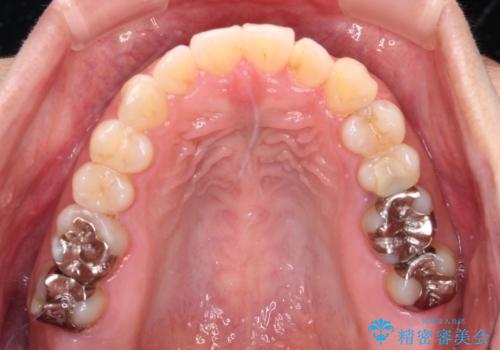

- 前歯の捻れを気にして来院された患者様です。

上顎前歯が捻れて前方に飛び出しており、下顎前歯もそれに沿うようにデコボコとなっていました。

IPR(歯と歯の間を削る処置)によりスペースを獲得して上下前歯のデコボコを改善し、インビザラインにて矯正治療を行うこととしました。

捻れていた前歯の形態が、先端が欠けていたり、一部むし歯処置により左右非対称の形態となっていたため、なかなかゴールが定まらず、治療期間がかかってしまいました。